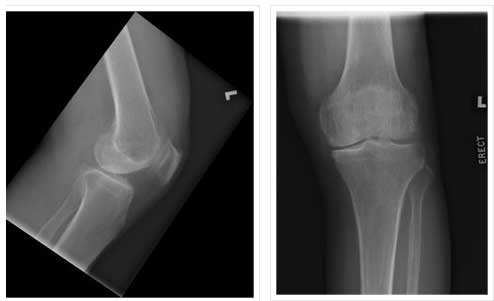

PATELLOFEMORAL ARTHRITIS IN- 40 YEAR OLD FEMALE

PATELLOFEMORAL REPLACEMENT-POSTOP